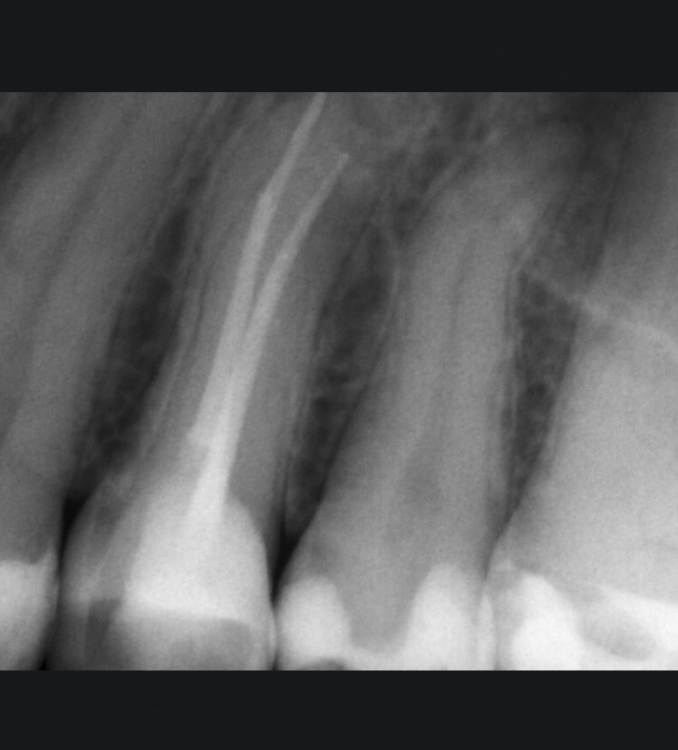

В конце прошлого года лечила каналы 4 зуба сверху. Зуб не болел и не беспокоил. В марте и в июле Ходила на снимок, зуба заживает но потихоньку. Доктор сказала понаблюдаем ещё, сделаем кт в декабре.

1фото сразу после лечения

длинный корешок, возможно потребуется резекция как сказал доктор ( пройти его не получится тк вышла небольшая перфо)